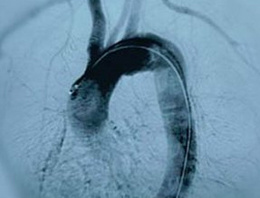

Halk arasında şah damarında genişleme ve balonlaşma olarak bilinen ve ailesel olarak çok sık görülen bir hastalık olmayan aort anevrizması, Erzurumlu Demir ailesinde 10 kardeşte de görüldü.

Yapılan incelemeler sonunda 10 kardeşin tamamında aort anevrizması olduğu ve kardeşlerden 7'sinin ameliyat sınırında olduğu tespit edildi. Kartal Koşuyolu Yüksek İhtisas Eğitim ve Araştırma Hastanesi'nden Uzman Dr. Altuğ Tunçer, Doç. Dr. Mesut Şişmanoğlu ve Dr. Özgür Aslan'ın takip ettiği ailenin iki üyesine, aynı anda hem aort anevrizması ameliyatı hem de bypass operasyonu yapıldı.

Dr. Altuğ Tunçer, "Damarlardaki genişlemenin çapı 5 santime gelince hasta ameliyat sınırına gelmiş olur. Ameliyat olmazlarsa büyük olasılıkla damar yırtılarak hastalar hayatını kaybeder" dedi. Dünya literatüründe benzer bir vaka olmadığını belirten Dr. Tunçer, "Türkiye'de de Erzurumlu 10 kardeşin hepsinde de aort damarı genişlemiş olarak bulunuyor. Şu anda 7 tanesi ameliyat sınırında. Bu dünya literatüründe bir ilk. Bu anlamda yapılacak genetik çalışmalar için de model bir aile olduğuna dikkat çekiyor" diye konuştu.

Aort anevrizması; normalde çapı en fazla 3.5 santim olan kalpten çıkan aortanın genişlemesi durumu.